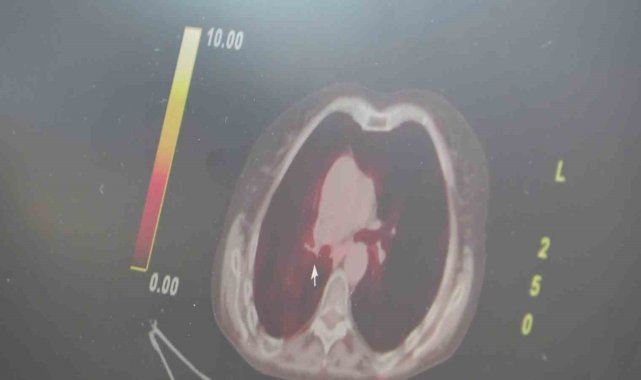

Cumhurbaşkanlığı Kabinesi'nin son toplantısında alınan kararla, ileri evre kanser tedavisinde kullanılan 5 akıllı ilaç SGK ödeme kapsamına alındı. Göğüs Hastalıkları Uzmanı Prof. Dr. Şevket Özkaya, bu gelişmenin kanserle mücadelede Türkiye'yi dünyaya örnek bir konuma taşıdığını belirtti.Cumhurbaşkanı Recep Tayyip Erdoğan başkanlığında gerçekleştirilen son kabine toplantısında alınan kararla, ileri evre kanser tedavisinde kullanılan ve dünyada modern tedavi olarak kabul edilen 5 akıllı ilaç, Sosyal Güvenlik Kurumu (SGK) ödeme kapsamına alındı. Artık hastalar bu ilaçlara ücretsiz ulaşabilecek.Konuya ilişkin değerlendirmelerde bulunan Göğüs Hastalıkları Uzmanı Prof. Dr. Şevket Özkaya, "Türkiye akciğer kanserinde dünyaya örnek olmaya devam ediyor. Özellikle ülkemiz dünyada en çok kanser görülen ülkeler arasında bir gruba aittir. Her 100 bin kişide 150 kişi kadar yeni kanser vakası ortaya çıkıyor. Bu vakaların büyük bir çoğunluğu akciğer kanseridir. Bütün dünyada olduğu gibi akciğer kanseri ülkemizde en sık görülen, en çok ölüme neden olan kanserlerin başında geliyor. Hastalarımızın çok kolay bir şekilde görüntüleme yöntemlerine ulaşıyor ve bizler de erken tanı koyabiliyoruz. Ülkemiz bu konuda dünyaya örnek olan bir ülkedir. Özellikle sosyal devlet politikası nedeniyle bütün hastalar bu radyolojik görüntüleme ve tanı yöntemlerine kolayca ulaşabiliyor. Akciğer ve bütün kanser türlerinde erken tanıyı kolayca koyabiliyoruz. Kanserde asıl problem kanseri önlemektir. Akciğer kanseri başta olmak üzere diğer kanserlere yol açan en büyük etken ise sigara olduğunu biliyoruz. Ülkemiz özellikle son 20 yılda cumhurbaşkanımız gayretleriyle sigarayla mücadelede çığır açtı. Toplum taşıma alanlarında, kapalı ortamlarda sigara ile mücadele ederek kanser vakalarına azaltmaya başlıyoruz. Ama yetmiyor. Kanser vakaları görmeye devam ediyoruz. Bunların büyük bir kısmı da ileri evrede geliyor. Kanserde kullanılan akıllı ilaç tedavisi tüm dünyada modern tedavi olarak biliniyor. Hastalar bu ilaçlara bireysel çaba ile ulaşabiliyordu. Cumhurbaşkanımızın son kabine toplantısında yaklaşık 25 kanser türüne etkili olan, dünyada artık modern tedavi haline gelen bu akıllı ilaçların 5 tanesi SGK ödeme kapsamına alındı. Hastalar hangi hastaneye giderse gitsin, bu 5 tane ilaca ücretsiz ulaşabilecekler. Önceden bu ilaçlara para ile ulaşabiliyorlardı veya mahkeme kararı bekleniyordu. İleri evre akciğer kanser başta olmak üzere bu 25 kanser türünün tedavisini devlet artık üstlenecek. Bu tüm dünyaya örnek olacak bir şey" dedi.Akciğer kanserini yenen hastanın uzun yıllar sigara içine pişmanlığıAkıllı ilaç ile akciğer kanserini yenen Neşe Ciğerim ise "4 yıl önce 4. evre akciğer kanseri olarak geldim. Akıllı ilaç önerdiler. Düzelmelerim başladı. Daha sağlıklı olmaya başladım. 34 ünite ilaç aldıktan sonra sağlığıma kavuştum. Akciğerde hiçbir şey kalmadı. İzi bile kalmadı. Eskiden çok sigara içiyordum. Çok pişmanım. Şimdi yolda sigara içenleri görünce durdurarak at şunu elinden diyorum" diye konuştu.